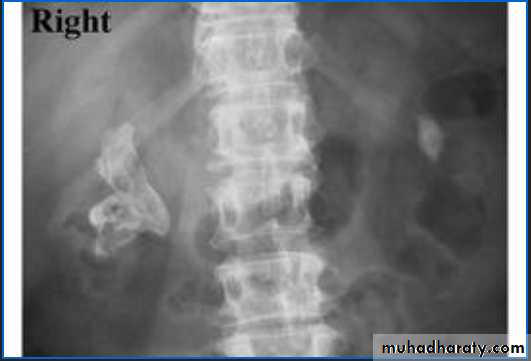

KUB.

Non visualization of the Rt. Kidney either due to early obst. Or type 5 renal injuryWhat's this imaging study?What the abnormal finding?